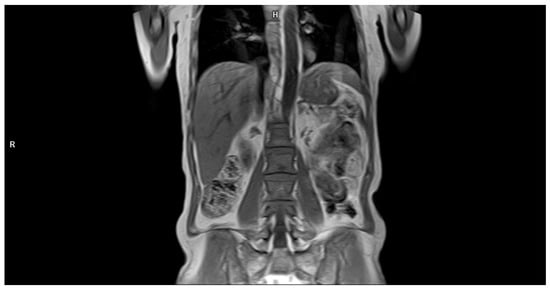

The presence of one or more sites of osteolytic bone destruction, at least 5 mm or greater in size, fulfills the criteria of bone disease in MM (CRAB), and therefore makes it necessary to initiate treatment (Figure 1, Figure 2 and Figure 3). In the case of smaller suspicious lesions seen in WBLDCT, they should be imaged within 3–6 months with CT or MRI to avoid overinterpretation [21,22].

Figure 5. Coronal T1-weighted image of a spine demonstrating a “salt-and-pepper” pattern of marrow involvement in a 63-year-old woman with a multiple myeloma diagnosis. Source: Radiological Diagnostics Center, The National Institute of Medicine of the Ministry of Interior and Administration, Warsaw, Poland.